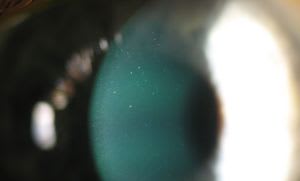

These photographs show mucin ball formation secondary to contact lens wear. The patient had been wearing his –1.50D OD and –1.75D OS Ciba Vision Night & Day lenses on an extended wear basis. He reported removing the lenses and sleeping without them once or twice a week. The patient replaced his lenses on a monthly basis. His visual acuity was 20/20 in both eyes, and he was asymptomatic. Mucin balls are thought to consist of collapsed mucin that results from mechanical interaction of a contact lens with the tear layer and corneal epithelium1,2. Mucin balls can indent the epithelium and pool fluorescein3. They should be differentiated from corneal microcysts, which are 10-micron to 50-micron vesicles that result from corneal hypoxia4. Mucin balls usually have no clinical consequence; in fact, they may be associated with decreased incidence of corneal inflammatory events5.